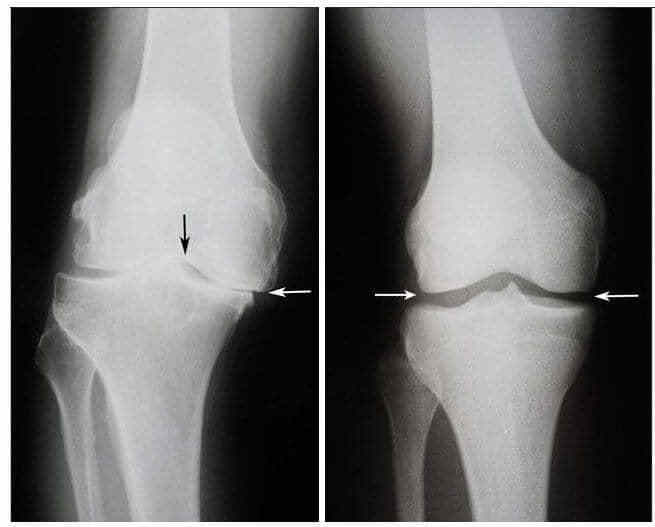

Тоді сталося диво. Після повного огляду лікар дав Валентині ці самі капсули про які всі говорять та наказав приймати щодня рано перед сніданком та перед сном. Через кілька тижнів вона змогла самостійно встати з інвалідного візка та піти до лікаря. Через шість тижнів ренгенні знімки показали що суглоби Валентини вдалось повністю вилікувати від остеоартриту.

Ліворуч: Знімок до лікування - хрящова тканина повністю зруйнована. Рекомендація лікаря – операція та заміна суглоба.

Праворуч: Знімок після лікування капсулами OsteoFix - суттєве поліпшення стану суглоба.